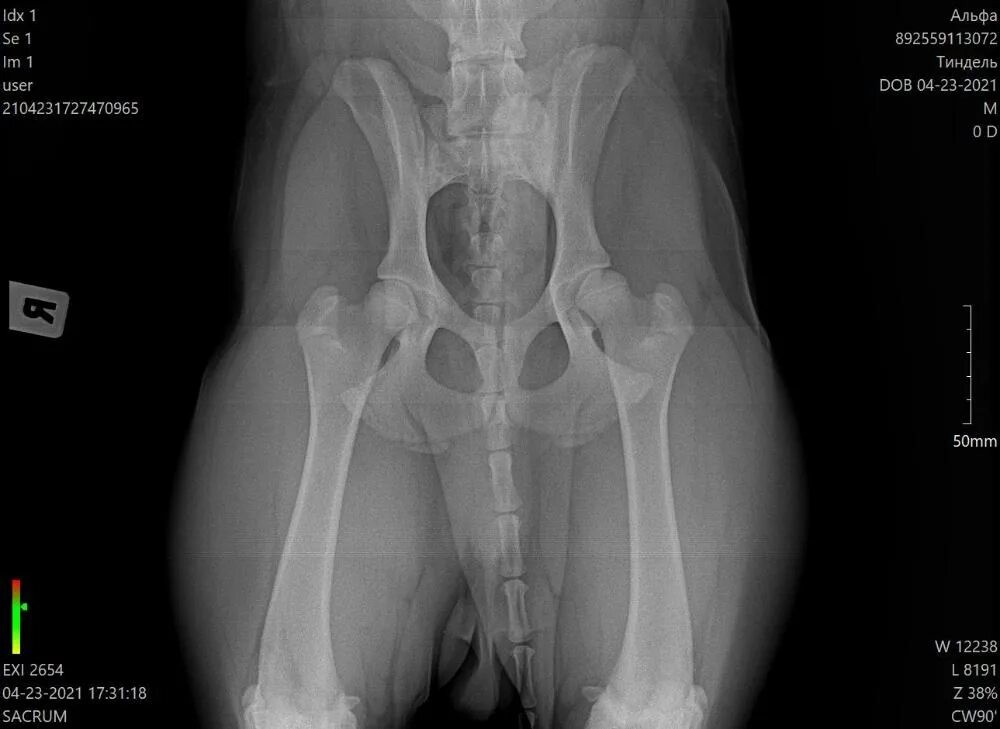

Дисплазия тазобедренного сустава мкб 10